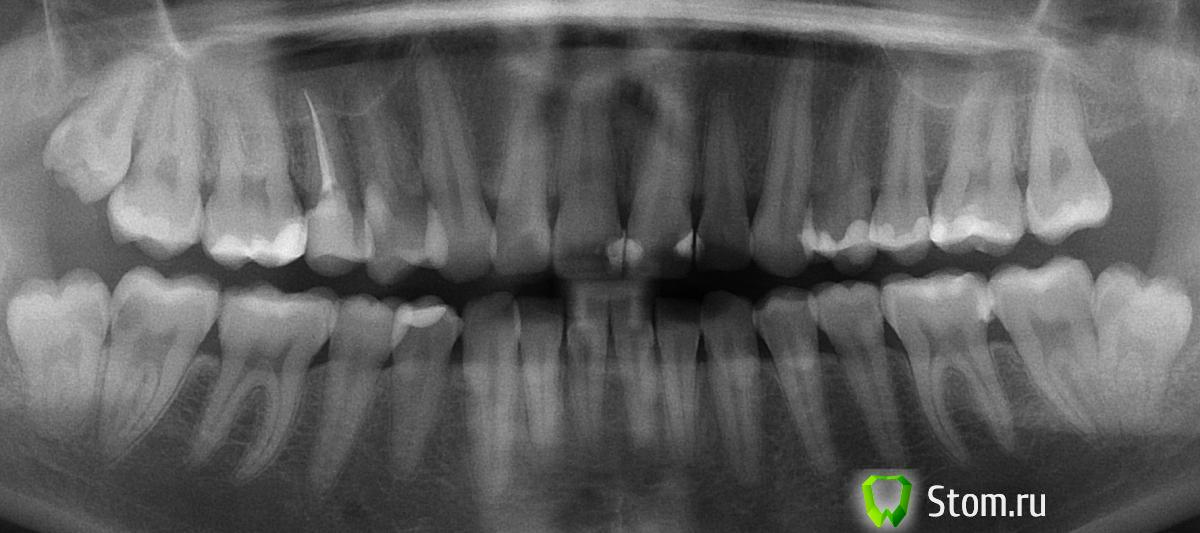

Елена Анатольевна Опубликовано 6 апреля, 2012 Поделиться Опубликовано 6 апреля, 2012 (изменено) 1. 48 и 18 удалены. нужно лечить 47 и 17 (кариес со стороны 8 ок). возможно ли сверление не сверху? зубы не болят. если в 47 придется удалять нерв что лучше коронка или стекловолокнонный штифт (в пломбе)? и если коронка то какая лучше? (коронку вообще не хочется)((((-: 2. на шейках зубов стерлась эмаль (штук 8) целесообразно ли их закрывать каким то матералом без сверления в клинике шадящей стоматологии( 3600 за зуб) или просто фторировать и все? заранее благодарю за консультациюЕлена Анатольевна4.bmp Изменено 6 апреля, 2012 пользователем Елена Анатольевна Ссылка на комментарий

Magdalena Опубликовано 8 апреля, 2012 Поделиться Опубликовано 8 апреля, 2012 чувствительность беспокоит иногда, а так ничего не беспокоит только лиш то что можно остаться совсем без эмали... один зуб мне лечили 10.12.10 при жевании он побаливает и если твердое что то ешь, ходила сто раз к врачу пломбу переделывали 5 раз результат тот же (закончли переделвать в июне 11), сделали вывод что пломба слишком близко к нерву и нужно либо удалять его либо ходить так.... хожу.... так может быть керамическая вкладка годится и в этом случае?Под оголением шеек можно подразумевать разные заболевания - клиновидный дефект, эрозия эмали, пришеечный кариес. Может приложите фото, чтобы разобраться? В любом случае беспричинно ни одно из перечисленных не появляется. И что там насчет щадящего лечения "без сверления"? По поводу зуба, где больно накусывать - приложите снимок, так, конечно, постпломбировочные боли вкладка сама по себе не снимет, надо искать причину Ссылка на комментарий